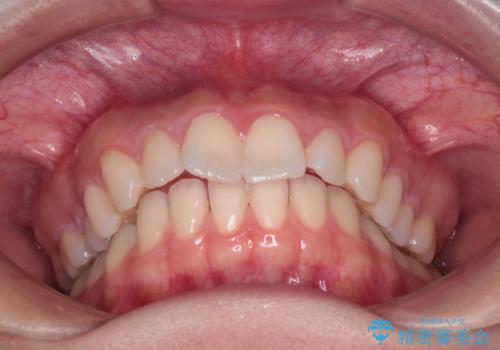

抜歯矯正をインビザラインで実現

- 患者様は、上下顎の歯列不正と前歯部の突出感を主訴としてご来院されました。診断の結果、上顎左右第一小臼歯を抜歯することでスペースを確保し、歯列全体を整える方針としました。本来はワイヤー矯正が推奨されるケースですが、患者様のご希望により、透明なマウスピース型矯正装置「インビザライン」を使用した治療計画を立案しました。治療期間は約3年で、奥歯の噛み合わせを維持しながら、徐々に前歯の位置を整えました。

インビザラインは見た目の目立ちにくさと取り外しが可能な点がメリットですが、複雑なケースでは治療計画の精密さが求められます。本症例では奥歯の噛み合わせが崩れないよう注意を払いながら、マウスピースの交換タイミングを細かく設定しました。患者様には装着時間を守っていただくことが重要で、1日20時間以上の装着が必須です。また、抜歯部位のスペースを閉じる過程で、歯の動きが停滞しやすい時期もあるため、定期的なチェックを通じて治療が順調に進むよう管理しました。